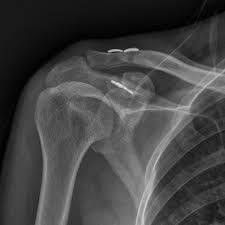

Οι τραυματισμοί 4ου - 5ου - 6ου βαθμού εξαρθρήματος κλείδας αντιμετωπίζονται χειρουργικά. Η χειρουργική αποκατάσταση διαρκεί κατά μέσο όρο 1 - 1 ½ ώρα και γίνεται με μία mini-open πρόσθια τομή στην περιοχή του ώμου 4 - 5 εκατοστών. Ο χρόνος του χειρουργείου θα πρέπει να γίνεται τις πρώτες 2 - 3 εβδομάδες από τον αρχικό τραυματισμό το αργότερο. Ο ασθενής που δε θα χειρουργηθεί έχει αυξημένα ποσοστά ανάπτυξης μετατραυματικής αρθρίτιδας της ακρωμιοκλειδικής που μεταφράζεται με πόνο και αδυναμία κατά την κίνηση του ώμου.

Η αποκατάσταση μετα απο την επέμβαση μετα απο εξάρθρωση στην κλείδα περιλαμβάνει ελεγχόμενη χρήση του άκρου τις πρώτες 3 εβδομάδες μετεγχειρητικά και στη συνέχεια ένα εξατομικευμένο πρωτόκολλο αποκατάστασης και κινησιοθεραπείας για την τελική ανάκτηση του πλήρους εύρους κίνησης.